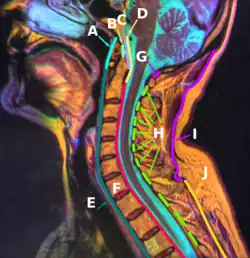

![]() Median sagittal section through the occipital bone and first three cervical vertebrae (ligament of apex dentis labeled at center left as apical odontoid ligament) | |

The ligament of apex dentis (or apical odontoid ligament) is a ligament that spans between the second cervical vertebra in the neck and the skull. It lies as a fibrous cord in the triangular interval between the alar ligaments, which extends from the tip of the odontoid process on the axis to the anterior margin of the foramen magnum, being intimately blended with the deep portion of the anterior atlantooccipital membrane and superior crus of the transverse ligament of the atlas.